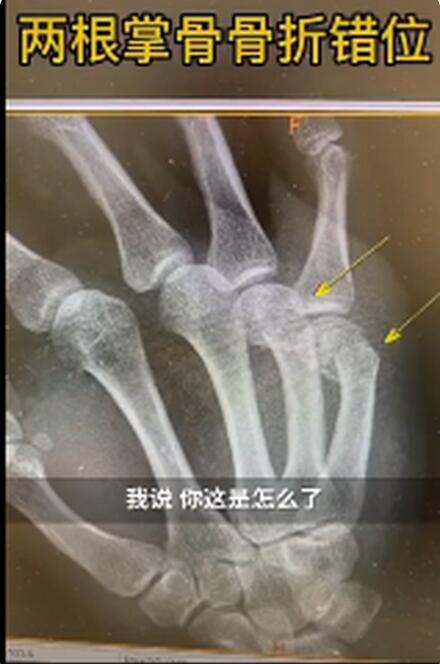

近日,上海新华医院骨科接诊了一男性患者。该患者右手第四第五掌骨肿胀明显。新华医院骨科主治医师王晖询问后得知,原来这名患者是在家辅导孩子作业时,因孩子作业做得不理想,生气但舍不得打孩子,自己捶墙,没想到把自己捶骨折了。